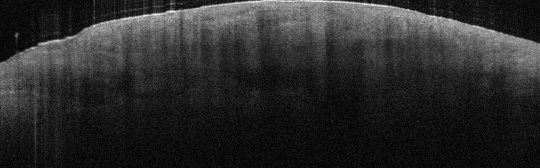

VA15: Right Dorsal Hand, Adjacent, Normal